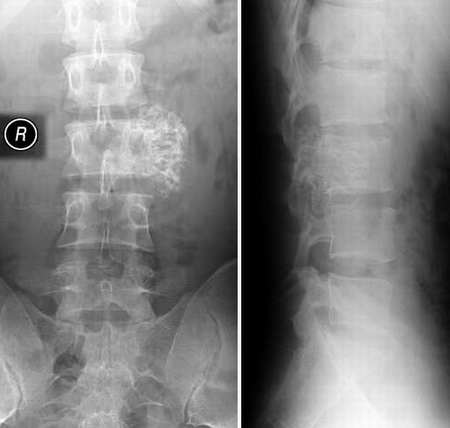

标题: X0180:腰椎,常见病,发生在不常见的位置。 [打印本页]

标题: X0180:腰椎,常见病,发生在不常见的位置。

腰3横突骨软骨瘤

完全同意骨软骨瘤,但起源部位倾向于椎板,从侧位上观察.

[emb6]腰3横突骨软骨瘤

[emb2]l3左侧横突——骨软骨瘤!

骨软骨瘤!发生在l3左侧横突__一个不常见的位置.谢谢分享!